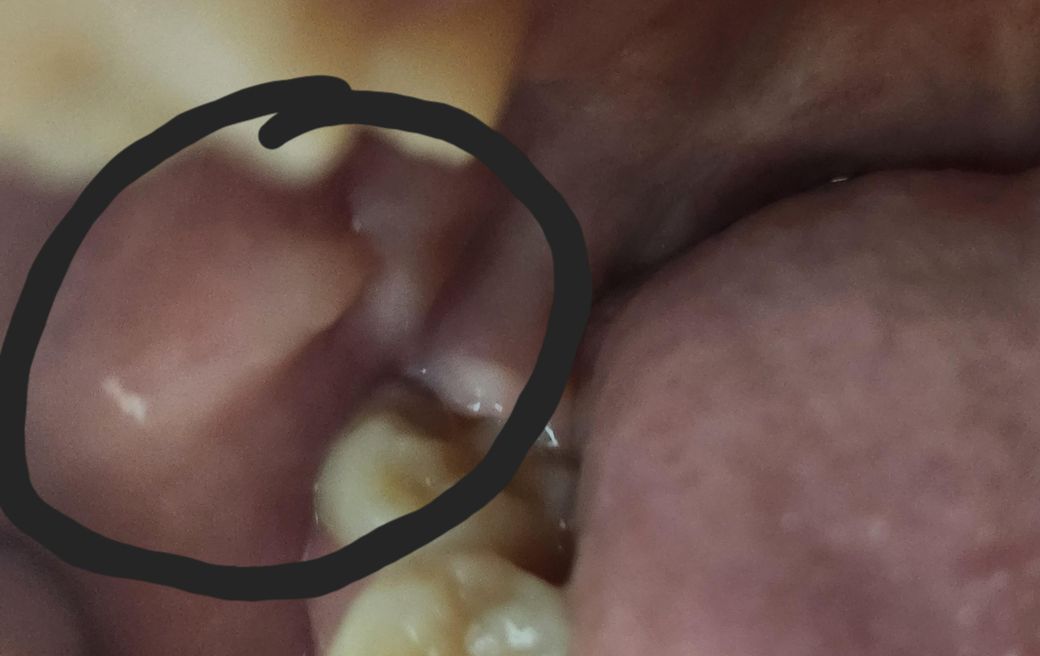

동그라미로 표시친 부분이 오른쪽 맨끝 어금니 위에 있는 볼 점막인데 찝힌 것처럼 상처가 생겼습니다 예전에 치과에서 어금니가 살짝 틀어져있어서 나중에 볼이 씹힐 수도 있다고 하셨는데 씹힌 상처 맞을까요?

볼살이 치아로인해서 씹혀서 조직이 늘어나는 것처럼 보입니다. 교합을 체크해보시면 좋겠습니다.

어금니 부위에는 힘을 너무 세게 주면 연조직이 내부로 말려 들어가게 되면서 볼이 씹히는 경우가 있습니다. 거기에 치아가 앞으로 나와 있다면 더 그런 증상이 발생할 수 있습니다. 음식을 먹을 때 치아의 힘이 덜 들어가게 한다면 해당 증상이 줄어들 수 있습니다.

사진에 보이는 부위는 볼살이 치아에 씹히면서 튀어나온상황입니다. 큰 문제가 잇는건 아닙니다.

보통 이갈이나 이악물기 등의 구강 악습관, 부정교합 등으로 저렇게 볼을 씹는 경우가 있는데요. 사실 저 자체로는 문제가 되지는 않지만 구강 악습관이 있는 경우 치아의 마모나 파절같은 손상을 일으킬 수 있기 때문에 이런경우는 처치를 해주시는 것이 좋습니다.

반복적인 볼 씹힘에 의해 자극이 되어 그렇게 생긴 것일 수 있습니다 다만 구강내 문제는 직접봐야 정확히 알 수 있습니다